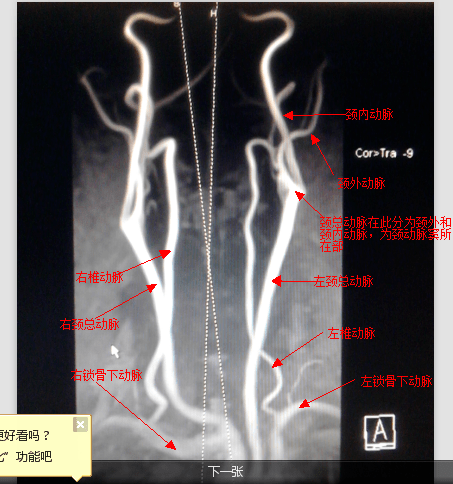

轻松看懂脑血管造影

五分钟看懂全脑血管造影